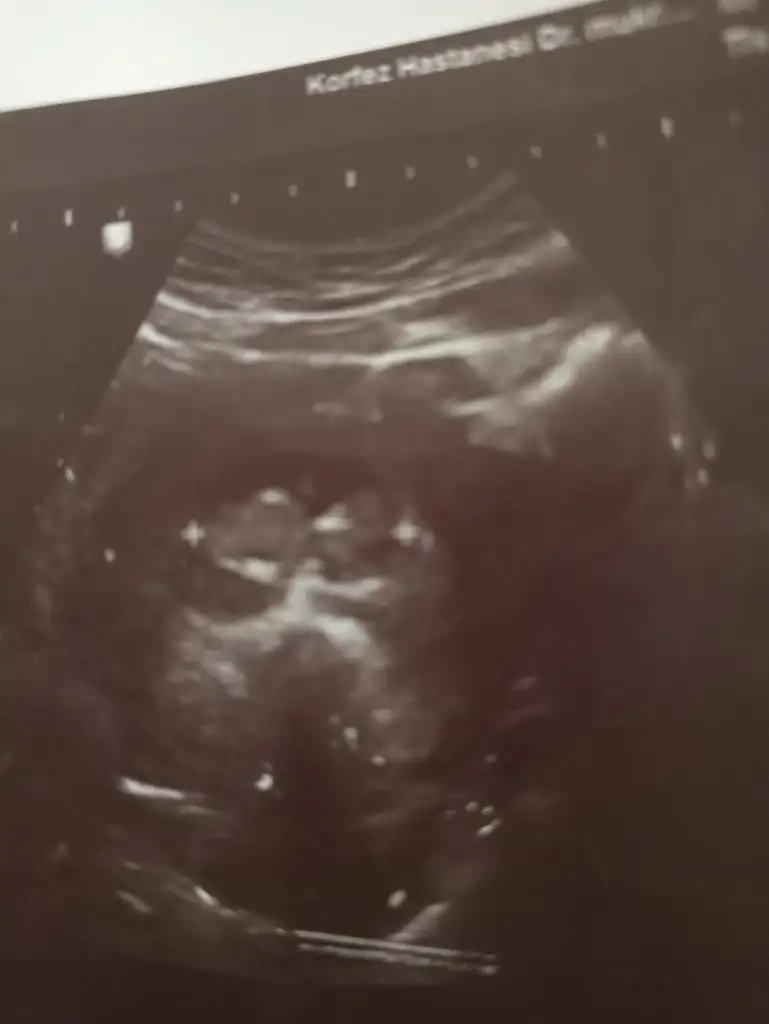

Canm 12 haftadayiz tahminde bulunur musun

• IMG20220801121845.webp

23,8 KB · Görüntüleme: 73

• IMG20220801120709.webp

57,9 KB · Görüntüleme: 74

• IMG20220801120653.webp

69 KB · Görüntüleme: 82